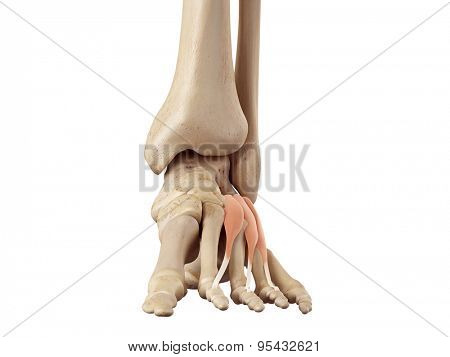

Extensor